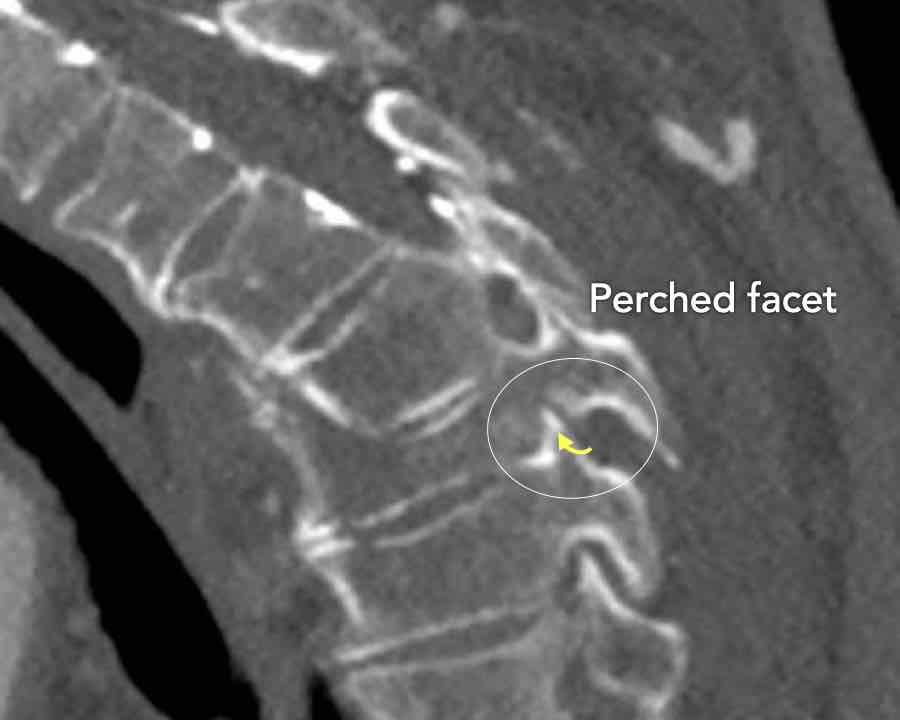

Scroll through the images

Findings:

- Perched facet joints (yellow curved arrows), so think of C injury.

- Posterior displacement of the vertebral bodies in the midline.

- Secondary A4 injury of the vertebral body.

Conclusion

Type C + A4 injury